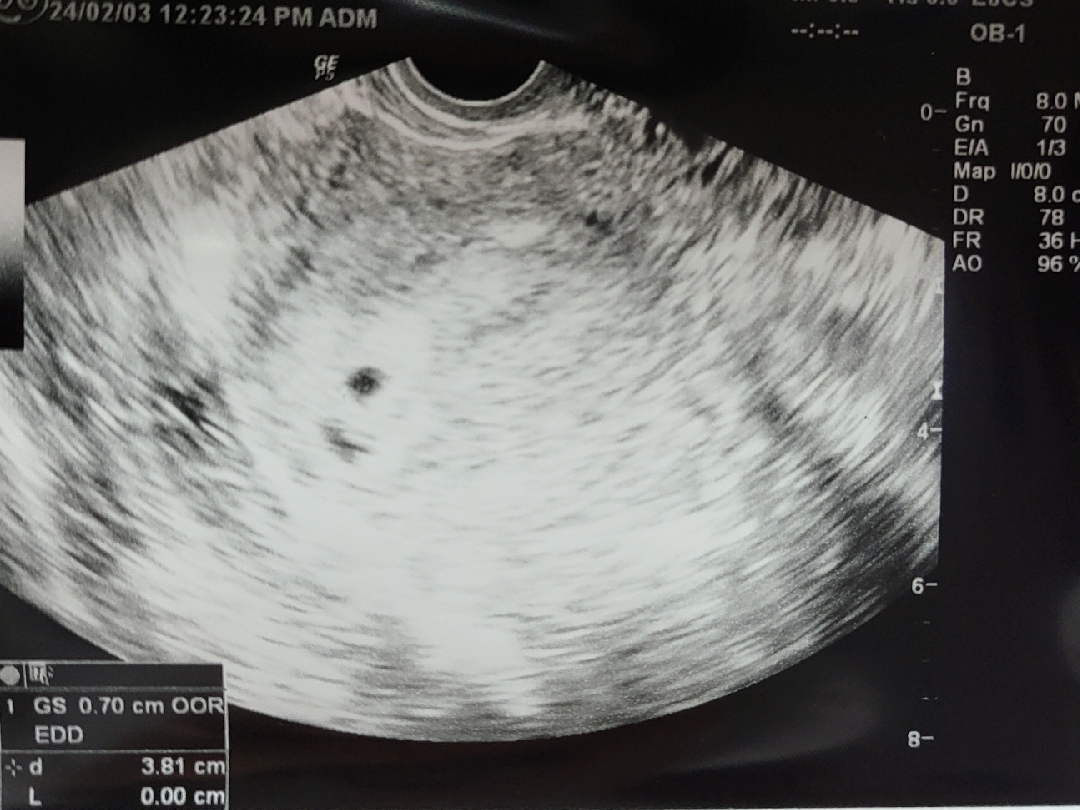

12월 28일 마지막 생리 시작일이고 1월 27일 임테기 확인 후 너무 이른느낌이라서 기다리다가 2/3일 오늘 병원가서 첫 초음파 확인하고 왔어요~!! 임신 5주 2일차로 10월 3일 출산일 받아왔네영 ㅎㅎㅎ 너무너무 신기하고 행복해요~!! 앞으로 할 일이 너무너무 많은데 첫시작은 바우처카드 발행인데 다들 바우처카드는 어떻게 발행하셨을까요? 꿀팁 알려주세용~!!